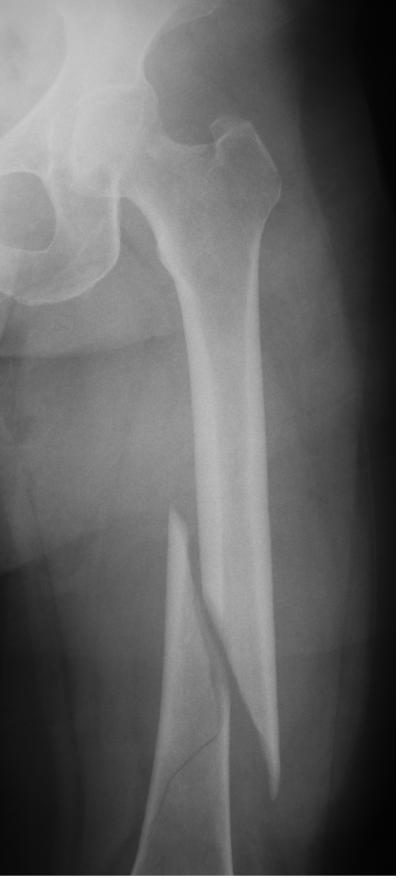

X-ray of right hip osteoporosis, age 54